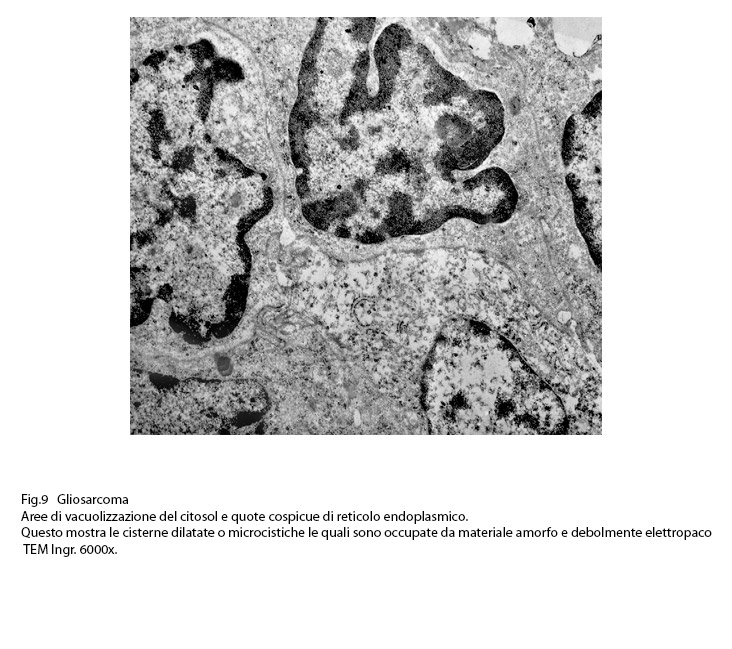

Anche il reticolo endoplasmico mostra segni ultrastrutturali di stress sia in associazione all’ergastoplasma sia in situazioni univoche.

Infatti,si repertano cellule di gliosarcoma con l’ ampio citoplasma occupato quasi interamente da queste formazioni; esse sono molto numerose, si trovano tra loro adese e mostrano le loro cisterne ectasiche o micro cistiche, creando così in una visione panoramica una immagine di aspetto cribroso .Lo spazio interno alle cisterne è apparentemente privo di contenuto, o, più raramente, è occupato da materiale amorfo, debolmente elettropaco.

Fig.9  Fig.10